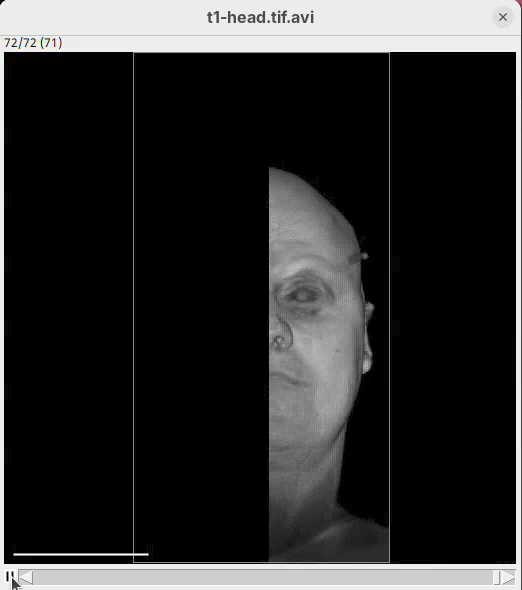

The BigDataViewer interface will open showing an optical section of the head sample.

Some of the movements to try:

Left-click and drag: turn the sample around the mouse pointer at any arbitrary angle.Right-click and drag: move the sample in the XY plane (of the view).Scroll: move through the Z plane (of the view). UseShift+Scrollto move fast.Ctrl+Shift+Scroll: zoom in or out.

But, most importantly, are the commands to put your sample back to its original orientation or along any of the original dimension axes:

Shift+Z: orient the sample on the XY plane.Shift+X: orient the sample on the ZY plane.Shift+Y: orient the sample on the ZX plane.

Finally, a visual tip. The default interpolation between image slices is nearest-neighbors. Press I to activate the tri-linear interpolation to obtain a much smoother (and improved) data visualization.